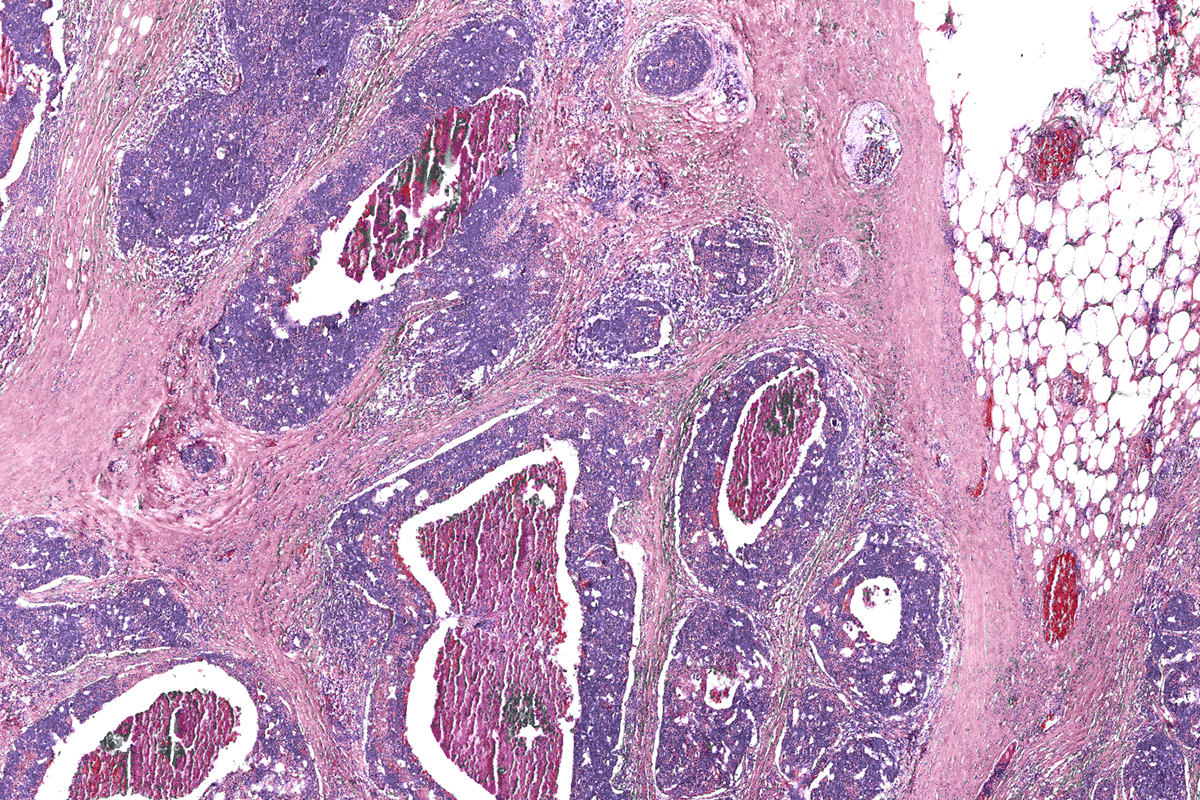

Cancer cells stained pink.

A ground-up approach to cancer research, staring with basic science and engineering, is the key to future clinical development — such as dye-free digital biopsies like this one, says Cancer Center at Illinois director Rohit Bhargava. Image courtesy of Rohit Bhargava